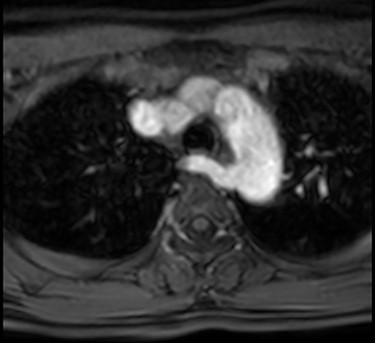

A preoperative magnetic resonance imaging (MRI) of the neck (Fig. 2) showed enlarged left lobe of thyroid with a solid nodule of 3.1 × 3.0 × 2.3 cm with mild mass effect on trachea. In addition, an aberrant right subclavian artery, taking a retro-esophageal, retro-tracheal course to the right upper limb was detected.

MRI with contrast showing right aberrant subclavian artery taking turn behind the trachea and esophagus.